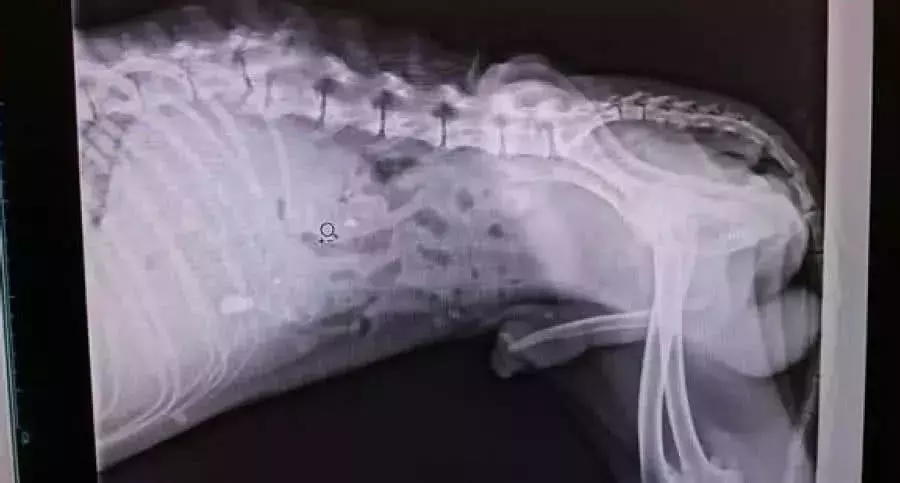

现在的流浪狗的问题似乎越来越严峻了 , 在大街小巷上 , 时常能看见它们饥肠辘辘的聚集在垃圾堆旁 , 翻找着能填饱肚子的食物 。 而对于救助措施不完备的我们来说 , 要做的就只是不要去伤害它们而已 。 那就算是这样 , 流浪狗们依旧过着非常惨的生活 。 有一只下身瘫痪的流浪狗就是这样 , 幸好被好心人发现 , 不然它可能过得比垃圾还惨 。